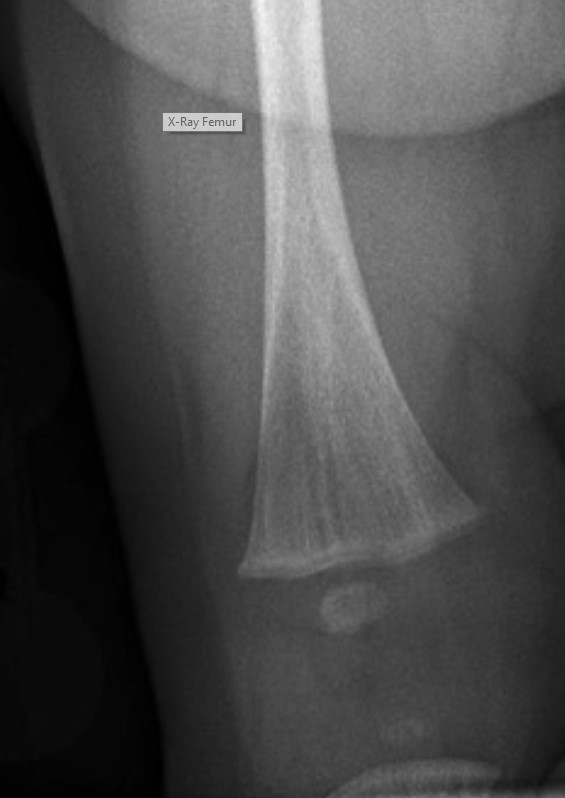

Røntgenundersøgelser viser

• Længdegående fortætninger i de lange rørknogler (i metafyser) (se figur) og bækken

• Sklerosing (fortykkelse) af bl.a. kranium og lange rørknogler